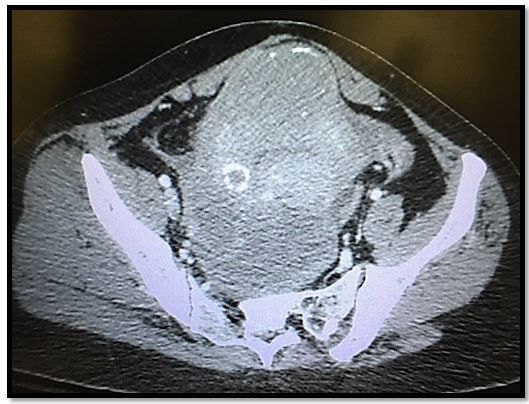

• CT scan pelvis: (click on Image to the right to enlarge)

Answers What does the case image show? The CT demonstrates a presacral fluid collection and incidental calcified fibroids. Radiology read: multiple uterine masses which are likely fibroids. Large loculated fluid collection in the cul-de-sac region. This was eventually determined to be a large tubo-ovarian abscess.